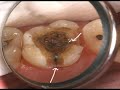

تشخيص المرض

التشخيص الطبي هو التشخيص في مجال الطب، وهو تحديد أي مرض أو حالة تسبب علامات وأعراض تظهر على الشخص ، و يطلق عليه ببساطة التشخيص في سياق الطب الضمني ، فهي كل عملية تعمل على تحديد المرض أو الحالة الموجودة وتسمى النتيجة التي يتم التوصل إليها من خلال هذه العملية "التشخيص" ( و على سبيل المثال، فإن عملية التشخيص يمكن أن تسفر عن تشخيص التهاب الحلق) ، أساس التشخيص دائماً يرجع لمعلومات من التاريخ والفحص البدني، ولكن في كثير من الأحيان قد يتضمن واحداً أو أكثر من الإجراءات التشخيصية، مثل الإختبارات التشخيصية،و التي تتم أيضاً خلال العملية.